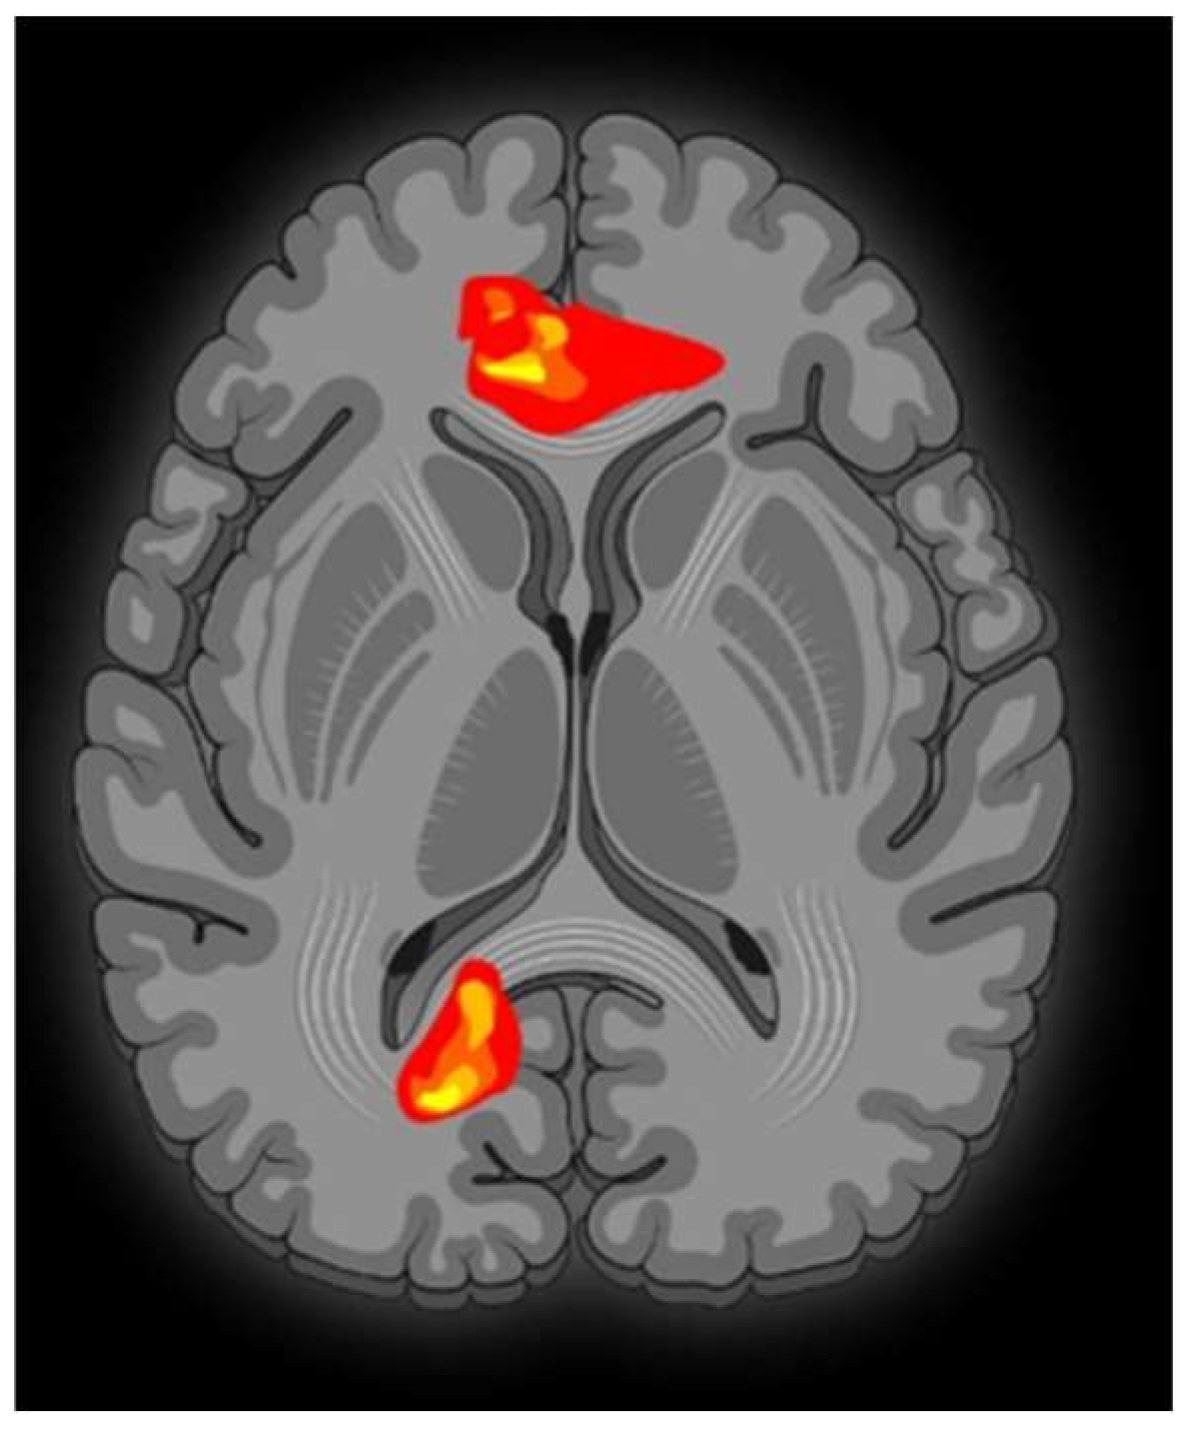

Contrasting minor with major melodies showed multiple activation sites (Figure 1) with the right parahippocampal gyrus (RPHG) being an eloquent brain area (Figure 2). Another discernible activation, when subjected to cluster-level correction, spanned both the left and right ventral anterior cingulate cortex (VACC) (BA 24) and extended into the left medial frontal gyrus (LMFG) within the medial prefrontal cortex (BA 10) (Figure 3). Remarkably, the inverse contrast (major over minor) did not yield significant activations. In a peak-voxel analysis, the response to the chromatic scale was intermediary when juxtaposed against the major and minor mode melodies for three of the aforementioned regions. These differential responses between the chromatic scale and melodies were not statistically significant, with an exception. Within the LMFG, the chromatic scale evoked the most prominent (least negative) response, trailed by the minor and subsequently the major mode. Notably, the contrast between the chromatic scale and the major mode was statistically significant in this context [25].

VACC activation is generally associated with affective processing, while its dorsal counterpart is linked with cognitive functions [26]. Moreover, the existing literature indicates that the VACC displays heightened sensitivity to emotional content characterized by negativity or sadness [27]. The observed engagement of the VACC might be consistent with the perception of minor mode melodies as possessing a sadder tonality in comparison to major melodies. Notably, prior neuroimaging research on mode-based contrasts has not reported VACC activation in contrasts between minor and major modes [28].

The detected involvement of the left medial frontal gyrus (LMFG) may be attributed to its robust neural connectivity with the anterior cingulate cortex and other limbic systems. Such a connectivity profile underscores the proposed function of the medial prefrontal cortex as an integrative nexus for emotional input from these associated regions [29].